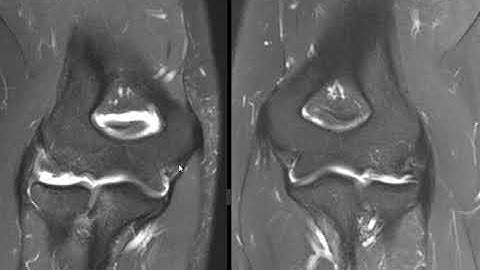

UCL tear from the sublime tubercle